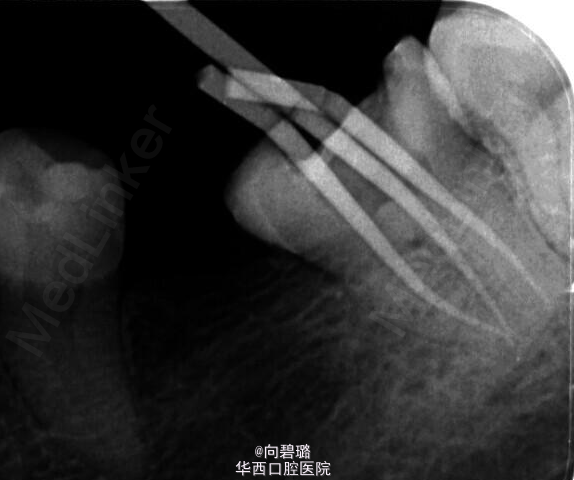

37牙根管预备过程中,由于其近中根疏通不畅,照片,牙胶失踪疑似底穿,加大投照角度依然如此。那么我们在临床工作中应该怎么样辨别底穿与否?首先X片是一个很直观的图像,一般来说可以从X片上看出来底穿与否(牙槽中隔是否有破坏或炎症性吸收),但是遇到磨牙三个根,四个根的情况时,由于投照角度的问题可能会不太好辨别,这个时候可以扩大探针看是否有出血,病人是否感觉疼痛,这都是一些辨别的手段。(来自:http://blog.kq88.com/88868.html)